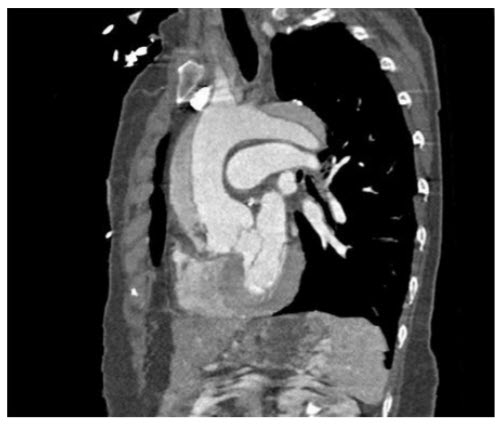

A TTE was performed showing a pericardial effusion and signs of cardiac tamponade. A CT angiogram is also performed and shown in figure below.

Controversy also exists regarding cardiac catheterization for patients with proximal aortic dissection. Proponents of cardiac catheterization argue that patients with severe obstructive coronary disease require grafting at the time of surgery and that failure to do so will increase the risk of perioperative and postoperative cardiac events. Those who favor not performing cardiac catheterization argue that any delay may increase the risk of death and that an invasive procedure will add further risk of dissection, tamponade, or rupture. One study comparing outcomes of patients undergoing surgery for aortic dissection found that those not undergoing cardiac catheterization had similar mortality than those undergoing the procedure. The 2010 guidelines for thoracic aortic diseases recommend that coronary angiography should be considered if the patient is over 40 years of age, stable, and has either known CAD, significant risk factors for CAD, or an ischemic presentation. Computed tomographic angiography of the chest. Sagittal oblique reconstruction shows an ascending aortic and aortic arch aneurysm with a dual lumen consistent with a type A aortic dissection (see figure in the question).